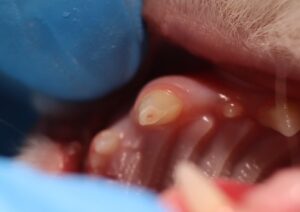

今回の症例:右上第四前臼歯の破折と露髄

この子は、硬いものを噛む習慣があり、ある日「歯が欠けている」と気づかれてご来院されました。

診察と歯科レントゲンにより、**右上第四前臼歯が破折し、神経(歯髄)が露出(露髄)**している状態と判明。